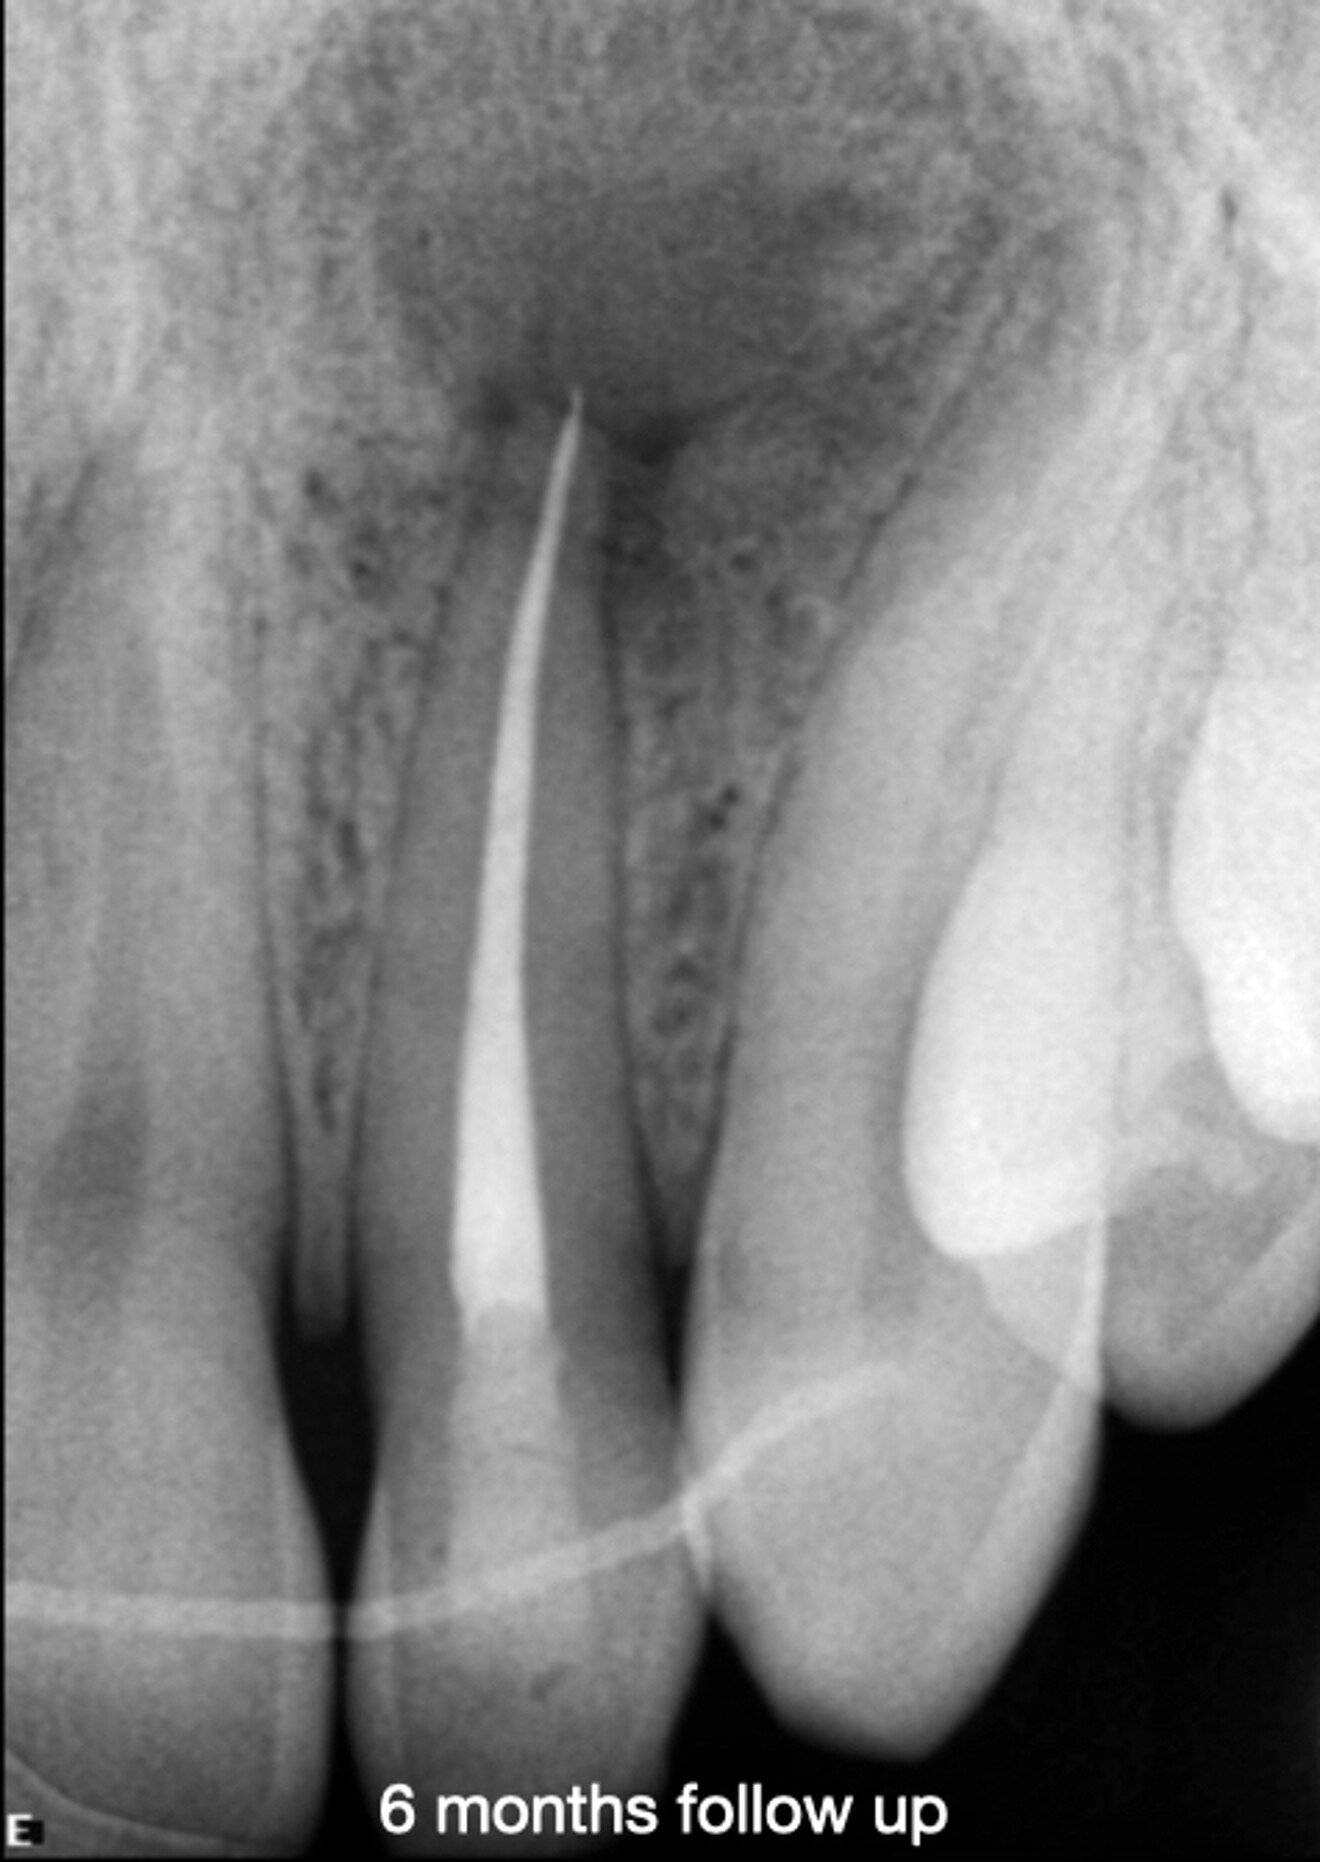

At the two-year follow-up appointment, the radiograph showed healing, but there appeared to be a superimposed image at the apex (Fig. 5). A high-definition CBCT scan taken with the DEXIS OP 3D showed that this was not a lesion but fibrous tissue consistent with physiological healing from the palatal area where the cortical plate had been largely damaged (Fig. 6). Since this was not pathological but a normal reparative process, there was no need to interfere.

Fig. 5b: Radiograph at six months.

Fig. 5c: Radiograph at two years, showing an area of less bone condensation at the root.